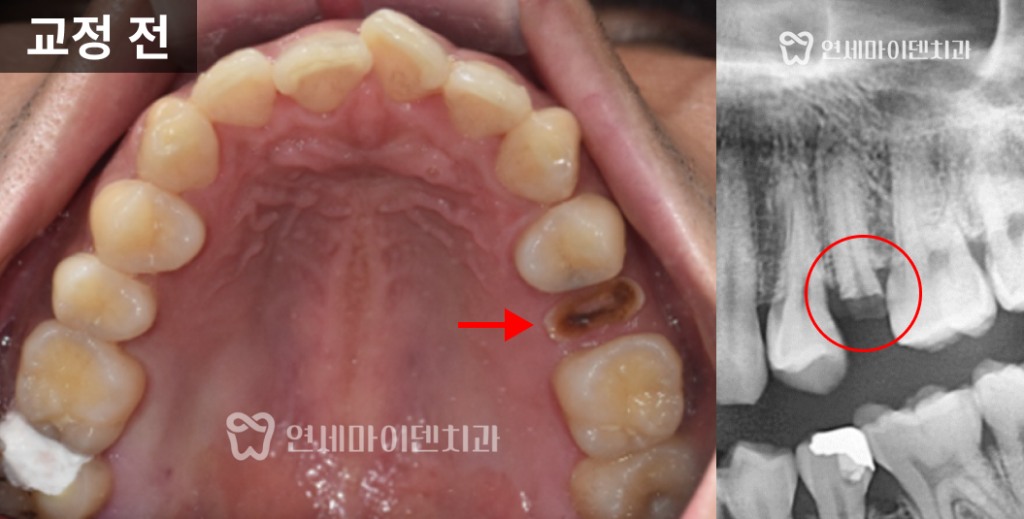

파절된 어금니는 치질이 거의 남아있지 않아서

바로 크라운을 씌울 수 없었습니다.

하지만 환자분이 30대 초반으로 젊으셨고

자연치 보존을 원하셨기 때문에

발치 후 임플란트 대신

치아를 정출시킨 후 크라운을 씌우는 치료 계획을 세웠습니다.

이렇게 함으로써 자연치를 가능한 한 오래 유지하면서

심미성과 기능성을 동시에 살릴 수 있도록 하였습니다.

위쪽의 깨진 어금니 부위는

교정 기간 동안 임시치아를 부착하여 사용하였습니다.

정출이 완료된 후 크라운을 장착하여

심미적으로도 완성도 높은 결과를 얻을 수 있었습니다.

정출 과정에서는 잇몸 건강에 무리가 가지 않도록

생물학적 폭경인 3mm 이내에서만 진행했습니다.